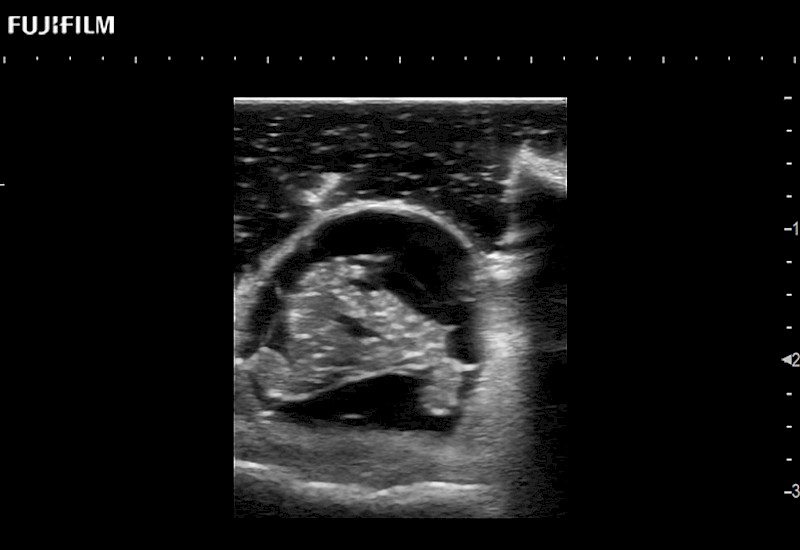

Tight curved (12mm) array transducer that is ideal for scanning during cranial guidance procedures.

Smaller footprint (20mm) curved array transducer that is ideal for scanning during cranial guidance procedures.

Exclusive 10mm side‐fire linear array transducer with 2.87mm diameter is ideal for real‐time visualization through and behind structures and instant, scalable definition of anatomy and vascularity including the ability to delineate and define tumor margins.